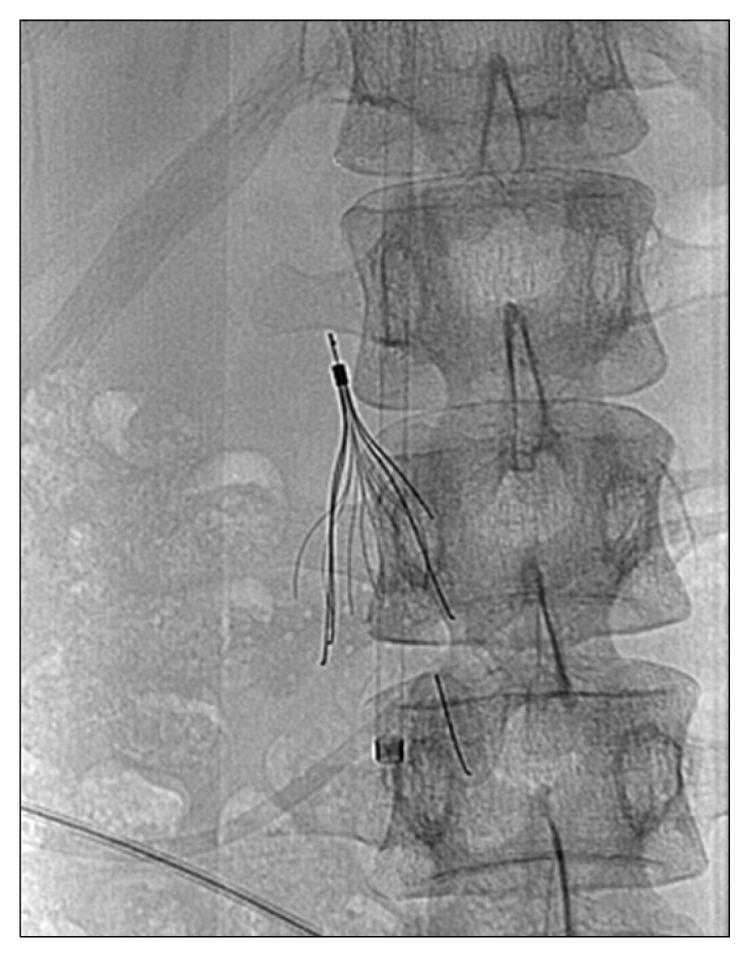

下腔静脉滤器支杆断裂后的血管外迁移

Extravascular Migration of a Fractured Inferior Vena Cava Filter Strut.

A 20-year-old man presented with a femur fracture and epidural hemorrhage (EDH) following a fall. One month after fracture surgery, swelling developed in both legs, and he was diagnosed as having a deep-vein thrombosis and pulmonary embolism. A retrievable inferior vena cava filter (IVCF) was inserted, because EDH is a contraindication to anticoagulants. Four months later, he complained of abdominal pain, and a computed tomography scan showed a fractured IVCF strut. After percutaneous removal failed 3 times, the IVCF was surgically removed by orthopedists using a portable image intensifier without cardiopulmonary bypass.

摘要

一名20岁男性在跌倒后出现股骨骨折和硬膜外血肿(EDH)。骨折手术后一个月,双腿出现肿胀,他被诊断为深静脉血栓形成和肺栓塞。由于硬膜外血肿是抗凝剂的禁忌证,因此植入了可回收下腔静脉滤器(IVCF)。四个月后,他主诉腹痛,计算机断层扫描显示IVCF支柱骨折。经皮取出失败3次后,骨科医生使用便携式影像增强器在无体外循环的情况下通过手术取出了IVCF。